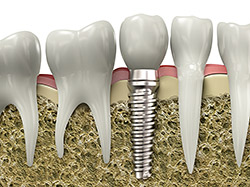

A dental implant is a synthetic tooth root in the shape of a post that is surgically placed into the jawbone. The “root” is usually made of titanium (the same material used in many replacement hips and knees), a metal that is well suited to pairing with human bone. A replacement tooth is then fixed to the post. The tooth can be either permanently attached or removable. Permanent teeth are more stable and feel more like natural teeth.